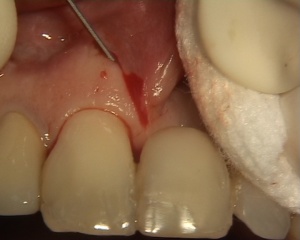

Supression d'un frein entre 11 et 21. Afin d'obtenir un meilleur rendu esthétique, un greffon est prélevé au niveau de la gencive vestibulaire, entre 12 et 13 et mis en place sur le site receveur.

Photos extraites de la vidéo :